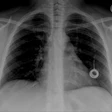

Boston Scientific nets CE Mark for Ingevity